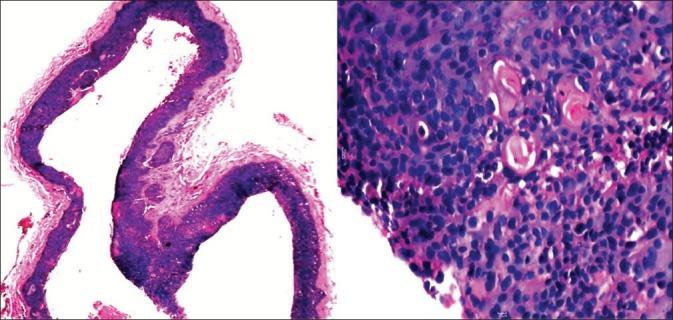

Sebaceous carcinoma is a rare neoplasm of the sebaceous gland. It is diagnosed mainly on histopathology and, clinically, it may mimic other neoplasms like squamous or basal cell carcinoma. We came across a patient presenting with a non-healing ulcer over the left temporo-parietal region of the scalp since 4 years and a single asymptomatic nodule over the occipital region since 3 years. Histopathology from an ulcer was pathognomonic of sebaceous carcinoma and that from a nodule was suggestive of proliferating trichilemmal cyst. The patient was screened for Muir Torre syndrome. We referred the patient to the oncologist for further management, where the patient was advised complete excision of the lesion.

皮脂腺癌是一种罕见的皮脂腺肿瘤。其诊断主要依靠组织病理学,在临床上,它可能会与其他肿瘤相似,如鳞状细胞癌或基底细胞癌。我们遇到一位患者,其头皮左颞顶区有一个4年未愈合的溃疡,枕部有一个3年的无症状结节。溃疡部位的组织病理学表现为皮脂腺癌的特征性表现,结节部位的组织病理学提示为增生性外毛根鞘囊肿。对该患者进行了穆尔-托里综合征的筛查。我们将患者转诊给肿瘤学家进行进一步治疗,肿瘤学家建议对病变进行完整切除。